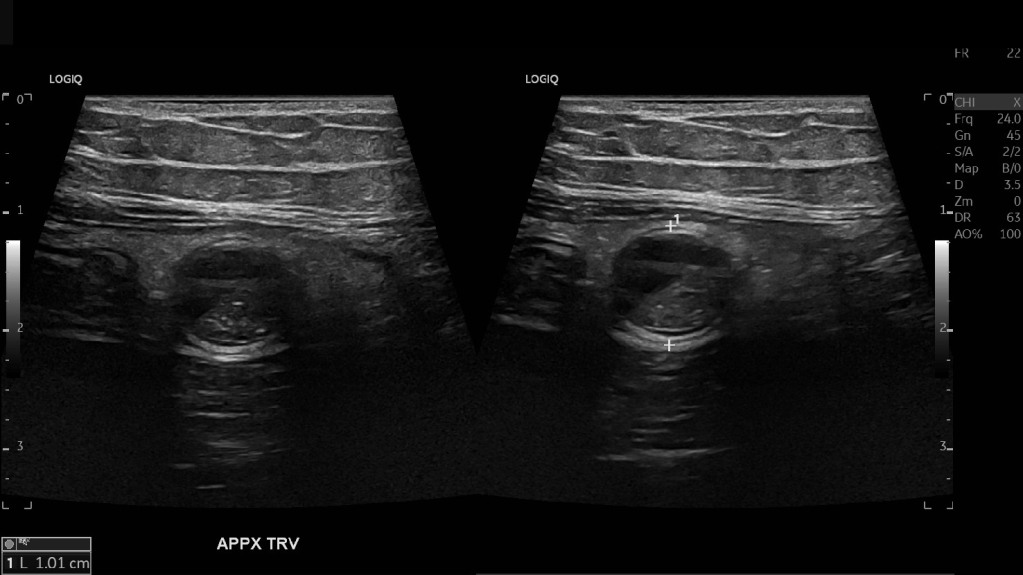

Appendicitis 13

Acute appendicitis @ 1 cm with L2-9mhz and L6-24mhz transducer GE Logiq e10.